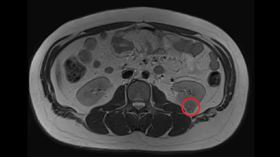

無不良嗜好 21歲男大生驚罹腎癌

年輕、看似健康、無不良嗜好的人,還是有可能罹癌。台中...